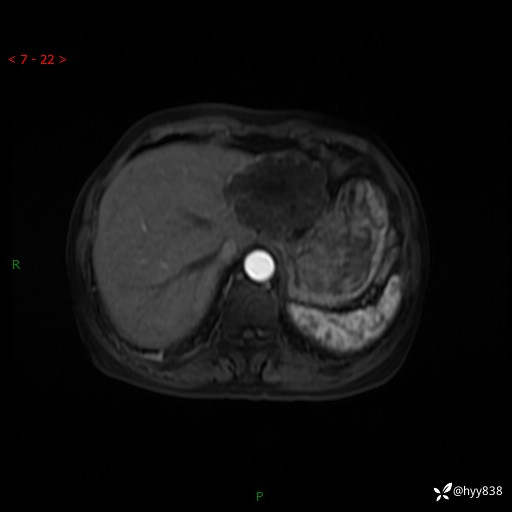

辅助检查:MRI

肝脏MRI平扫(同反相位)

T2WIfs+DWI

增强(动脉期+静脉期+延迟期)